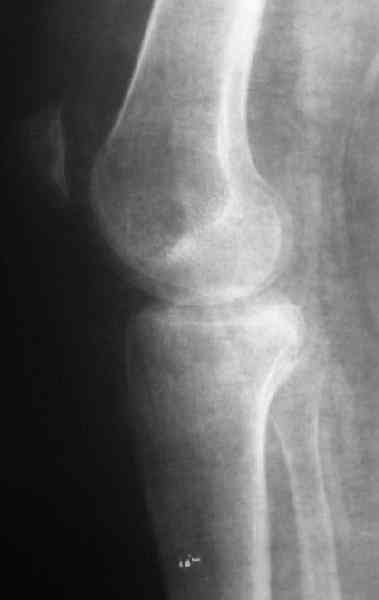

По тактике лечения, более импонирует второй вариант, но наружная плато расколота и туда при нагрузке внедряется н/мышелка бедра, поэтому после дистракции как репонирвать: или стяжными винтами, или изогнутами спицами или субхондральная костная пластика?

Уважаемый Абдурашид. Если нет противопоказаний , то из оперативных способов, я бы рекомендовал следующие: Полное замещение наружного мыщелка аллотрансплантатом либо открытая репозиция с элевацией и замещение дефекта ауто или аллокостью. В Ваших условиях , я бы рекомендовал второй способ. Во-время элевации необходимо разъединить фрагменты со стороны сустава ( надсечь скальпелем по линиям перелома, а затем тонким остеотомом их разъединить. При помощи долота произвести неполную остеотомию ( захватите не менее 1,5 - 2 см губчатой кости и поднять фрагменты, визуально отрепонировать и фиксировать 2-3 спицами. Дефект заместить костным ауто или аллатрансплантатом. Окончательная стабилизация пластиной ( лучше с угловой стабильностью, либо АВФ - позволит спокойно устранить угловую деформацию.